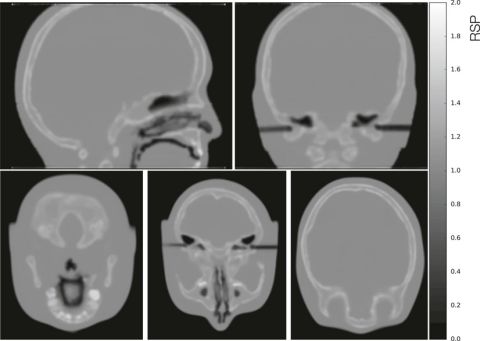

I tillegg er Helge aktiv innan utvikling av proton CT i samarbeid med Universitetet i Bergen mfl., ein framtidig modalitet for å direkte måle korleis protona stoppar i pasienten, med mål om å gjere protonterapi meir målretta og slik redusere seinskader. Helge sitt bidrag er datasimulering av detektordesign og utvikling av programvare for bilderekonstruksjon.

Partikkelterapi setter store krav til nøyaktig diagnostikk. Under behandlingen bestråles pasienten med protoner eller tyngre ioner. Partiklene ioniserer molekyler i vevet, og stopper gradvis opp. Akkurat hvor de stopper bestemmer hvordan stråledosen gis til pasienten, og det er da nødvendig å kjenne pasientens stoppekraft. Det finnes ulike måter å beregne stoppekraften på, og dagens metode går ut på å bruke pasientspesifikke målinger fra en kalibrert CT.

I Bergen utvikles en detektor som kan måle stoppekraften direkte, ved hjelp av å måle energitapet til høyenergetiske protoner som sendes rett gjennom pasienten. Da kan man mer nøyaktig anslå stoppekraften, og partikkelterapi-behandlingen blir mer presis gjennom reduksjon av det bestrålte friske området rundt tumor. En slik detektor kan også brukes for å kontrollere pasientposisjon fra strålens perspektiv, samt verifisere at pasientens totale stoppekraft er uendret før behandling.

Detektoren består av komponenter for å måle retning og posisjon til protonene (for å finne den buede banen gjennom pasienten), og for å måle hvor mye energi protonene har tapt i pasienten. I Bergen benyttes kunnskap og metoder fra partikkelfysikk-laboratoriet CERN for å utvikle og bygge en proton CT-skanner: den består av 43 lag med høyoppløste pikseldetektorer som kan spore hundrevis av samtidige protonbaner, samt elektronikk for å lese ut og analysere de enorme datamengdene.

Prosjektet er et samarbeidsprosjekt mellom blant annet Universitetet i Bergen, Høyskolen i Bergen, Haukeland Universitetssykehus og flere internasjonale partnere i Nederland, Tyskland, Ungarn, Ukraina, Kina og Thailand. Gruppen har mottatt midler fra bl.a. Norsk Forskningsråd (TOPPFORSK) og Trond Mohn Stiftelse.

Diagram

En skjematisk oppsetning av proton CT detektoren.  Det er en lagdelt detektor med 2 tynne sporingslag og 41 tykkere sporingslag for å måle energien til hvert proton. Oppsettet er vist med nødvendig kjøling og utlesningselektronikk. Alme et al. 2020.

En collage av innsiden av en menneskeskalle

Et rekonstruert tomografi av et hodefantom, bestrålt av 790 millioner simulerte protonbaner, målt med en datamodell av detektoren. Alme et al. 2020.